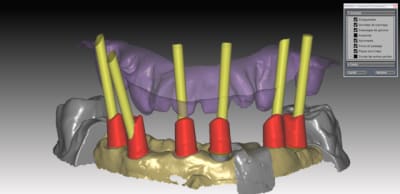

donc voici comme promis piliers ZR sur base Titan

passivité total de l'armature , les piliers sont tous réglés , parallélisés lors de la modélisation de l'ensemble . l'usinage des piliers et de l'armature ce fait séparement pour encore qualité d'ajustage..

Dans le ce cas present Strauman BL 3.3 rc

collage des base titan avec du multilink automix

ce cas est en cour de réalisation , essayage de l'ensemble

déja validé ... je n ai pas de eu de photos , aucun blanchiment de gencive , merci l'ajustage des profils d'émergence dans le soft qui est vraiment bien fait ..

le ptit dernier pour la route

IMPLANT NB REPLACE

nouveauté du system . 2 ccZR transvissées SOLIDARISEE sans base titan

sur des connections interne....

J insiste sur la possibilité et l'avantage de régler les profils d'émergences . de un, on epouse parfaitement la gencive sans trop la mal traiter , et de 2 l'aspect final des couronnes s'en ressent car on a beaucoup moins cet effet de cintrage au collet de la dent qui souvent donne des etrangetées morphologique .

Vous pouvez voir également le puit ( en occlusal)qui depasse de la structure et qui epouse la morpholgie de la ceramique à venir .. assez sympa et bien pratique pour vous lors du rebouchage avec le compo ...